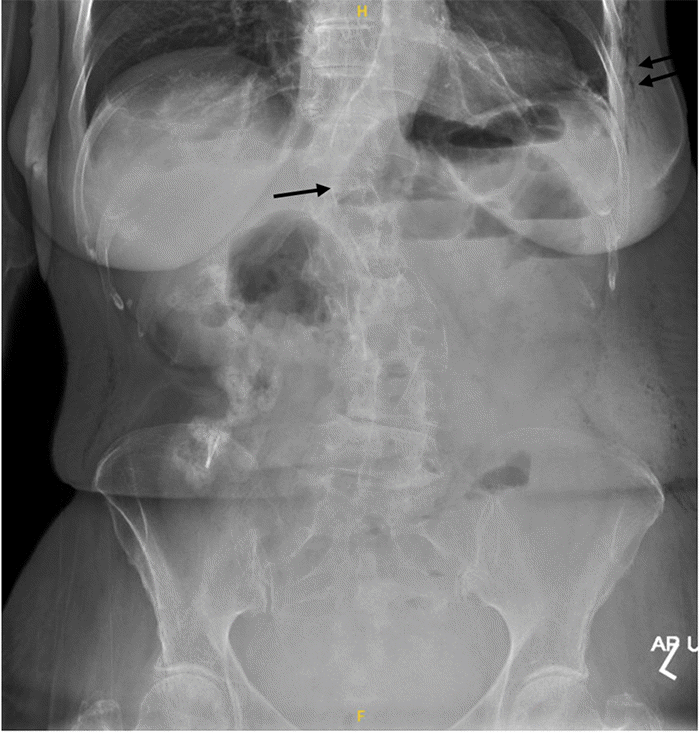

On postoperative day (POD) 2, after ambulating, the patient developed a firm, painful bulge at the LAAL 6 mm port site. She had not yet had a return of bowel function. Examination revealed a soft, non-distended abdomen with tenderness localized to this port-site bulge, which was initially suspected to be a hematoma. Abdominal X-rays obtained on POD 2 showed minimally dilated small bowel loops in the LUQ, no pneumoperitoneum, and diffuse subcutaneous emphysema throughout the left abdominal wall soft tissues (Figure 2). The lack of bowel function was attributed to resolving postoperative ileus, and she was continued on a full fluid diet. However, on POD 5, she began to vomit. A CT scan of the abdomen and pelvis with oral and intravenous contrast was performed, which demonstrated a high-grade SBO secondary to a port-site hernia at the LAAL 6 mm trocar site (Figure 3), with no evidence of bowel ischemia.

Figure 2. Abdominal Radiograph on Postoperative Day 2. Published with Permission.

Abdominal radiograph obtained on POD 2. The image demonstrates minimally dilated small bowel loops in the left upper quadrant (single arrow) and diffuse subcutaneous emphysema throughout the soft tissues of the left abdominal wall (double arrow)